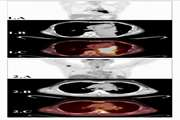

Computed tomography pulmonary angiography (CTPA) for the detection of pulmonary embolism (PE) among trauma patients: a systematic review and meta analysis Jul 15 2025 - 10:03